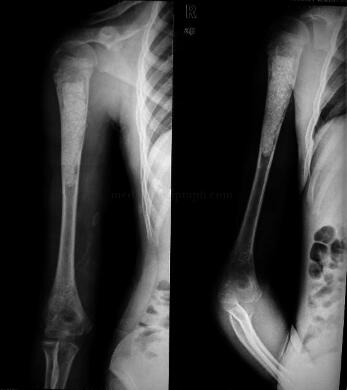

1. 选择X线检查的原因 了解病变性质及有无骨折,在诊断中有着不可替代的作用(图78-1)。

2. 检查结果 病变位于右肱骨近端干骺端,呈单房均匀透亮轴向椭圆形囊性变,病灶处骨皮质变薄,边界清晰,可见骨折线。

图78-1 右肱骨上段及肱骨干透亮轴向囊性变,骨皮质变薄